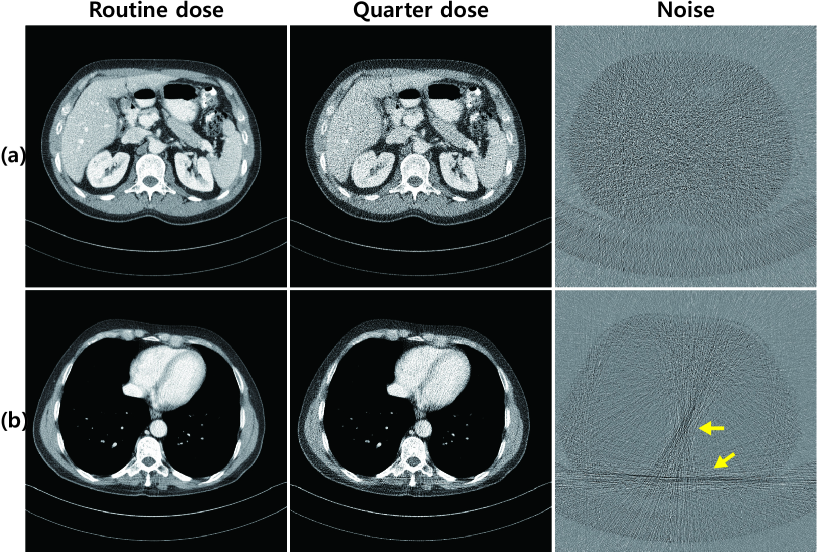

Refer to caption

Figure 1: Various noise patterns in low-dose CT images: (a) Gaussian noise, and (b) streaking artifacts

In practice, polychromatic X-ray can produce various artifacts such as beam-hardening. Given that the lower energy X-ray photons are seldom measured by detectors, the linearity of the projection data and attenuation coefficients is no longer valid. In addition to these beam-hardening related artifacts, there are photon-starvation artifacts because bones have higher attenuation and thus absorb a considerable amount of X-ray photons. Specifically, ribs and backbone are located on opposite sides of the body; therefore, an X-ray beam should pass through more than two bones depending on the direction of the X-ray path such that we lose information about the tissues between these bones. This results in streaking artifacts in these directions (see Fig. 1).